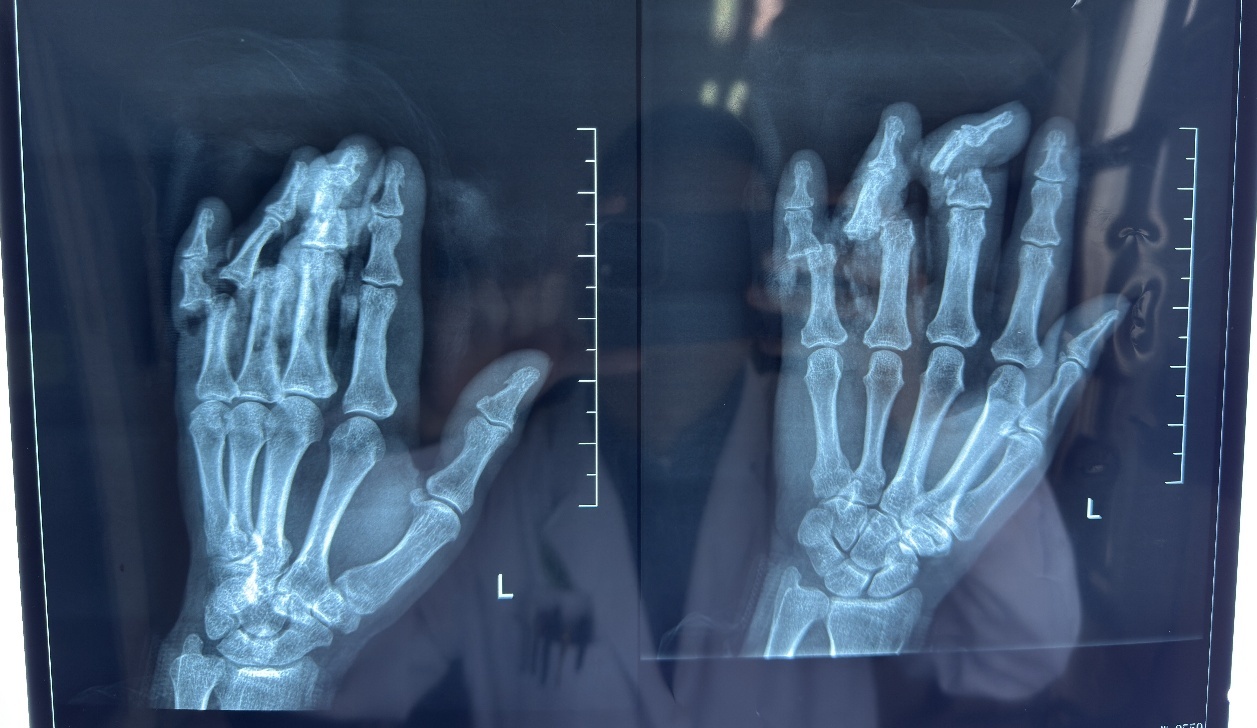

快一分钟就多一分手指接成功的概率。患者转运至中大医院后,医院立即启动救治绿色通道,急诊医护人员第一时间联系烧伤整形科会诊,迅速为患者完善影像学检查。“患者左手3、4、5指完全离断,局部挫伤严重,仅残余部分皮肤及软组织连接。”接诊患者的烧伤整形科王柯医师介绍。检查结果明确显示:患者左手中指骨折,左手环指中节骨基底旁见小片状骨性密度影,左手第4、5指近节关节脱位。